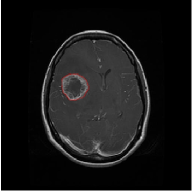

From the above discussions, we have discovered the significant potential of applying Retinex theory to image segmentation and explored its fundamental differences from traditional models. Traditional image segmentation models typically focus on the impact of intensity information on the segmentation results. Therefore, when faced with complex segmentation scenarios, the segmentation results are often affected by lighting, artifacts, and unclear boundaries in the image. As shown in Fig. 1, we present the results of the classical local model LIF [ZHANG20101199] for segmenting brain tumor images along with surrounding tissue edema. The irregular ring-like enhancement caused by the edematous tissue leads to irregular boundaries and low contrast in the images. Consequently, the LIF model can only identify the central necrotic and liquefied regions of the tumor, failing to detect the boundaries and becoming trapped in local minima. In this paper, we draw inspiration from the Retinex theory, which is widely applied in the field of image enhancement. According to Retinex theory, the reflectance component characterizes the intrinsic structural properties of the observed image and preserves texture information independent of illumination variations. By integrating this reflectance component into the level set framework, our model achieves robust segmentation of medical images even under severe intensity inhomogeneity. In addition, a linearized Structural-Prior is proposed to restore intensity consistency and capture local geometric features, thereby improving boundary localization in complex or blurred regions. Furthermore, a relaxed binary level set representation is employed to enhance robustness against noise and to enable accurate tracking of complex contours. Based on these innovations, we propose a novel variational reflectance-based level set model (RefLSM) that simultaneously corrects bias fields and performs segmentation. Experimental results demonstrate that RefLSM significantly outperforms conventional level set methods in both segmentation accuracy and robustness. We present the results of our model segmenting the two brain tumor images mentioned above in Fig. 2.

To address the challenge of segmenting images with severe intensity inhomogeneity, we propose a linearized structural prior that directly operates on the reflectance component . Reflectance-based structural information is more robust to illumination variations and bias field distortions, helping preserve weak edges and subtle anatomical boundaries. As shown in Fig. 2, our method can accurately delineate tumor boundaries and surrounding edema even under severe inhomogeneity, where traditional intensity-based models often fail. The proposed prior aligns smoothed reflectance gradients with data-driven directions, enhancing inter-region contrast, preserving weak edges, and stabilizing the evolution of . Formally, we define the linear structure operator as the gradient field of the smoothed reflectance: